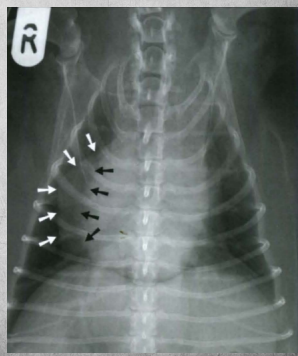

(white arrows point to fat around heart edge which is marked with black arrows)